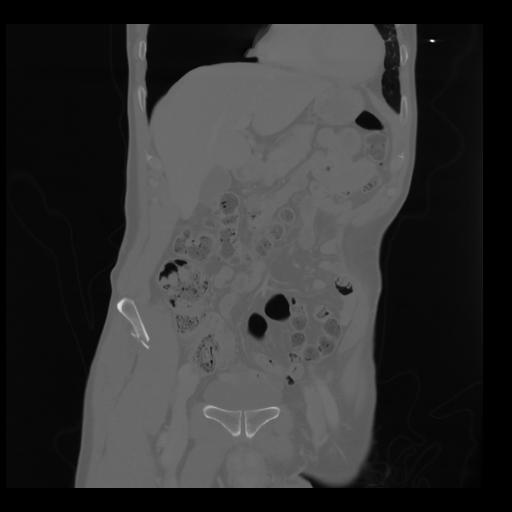

35 CUERPO,CE,Coronal,3.000,CUERPO,Coronal,